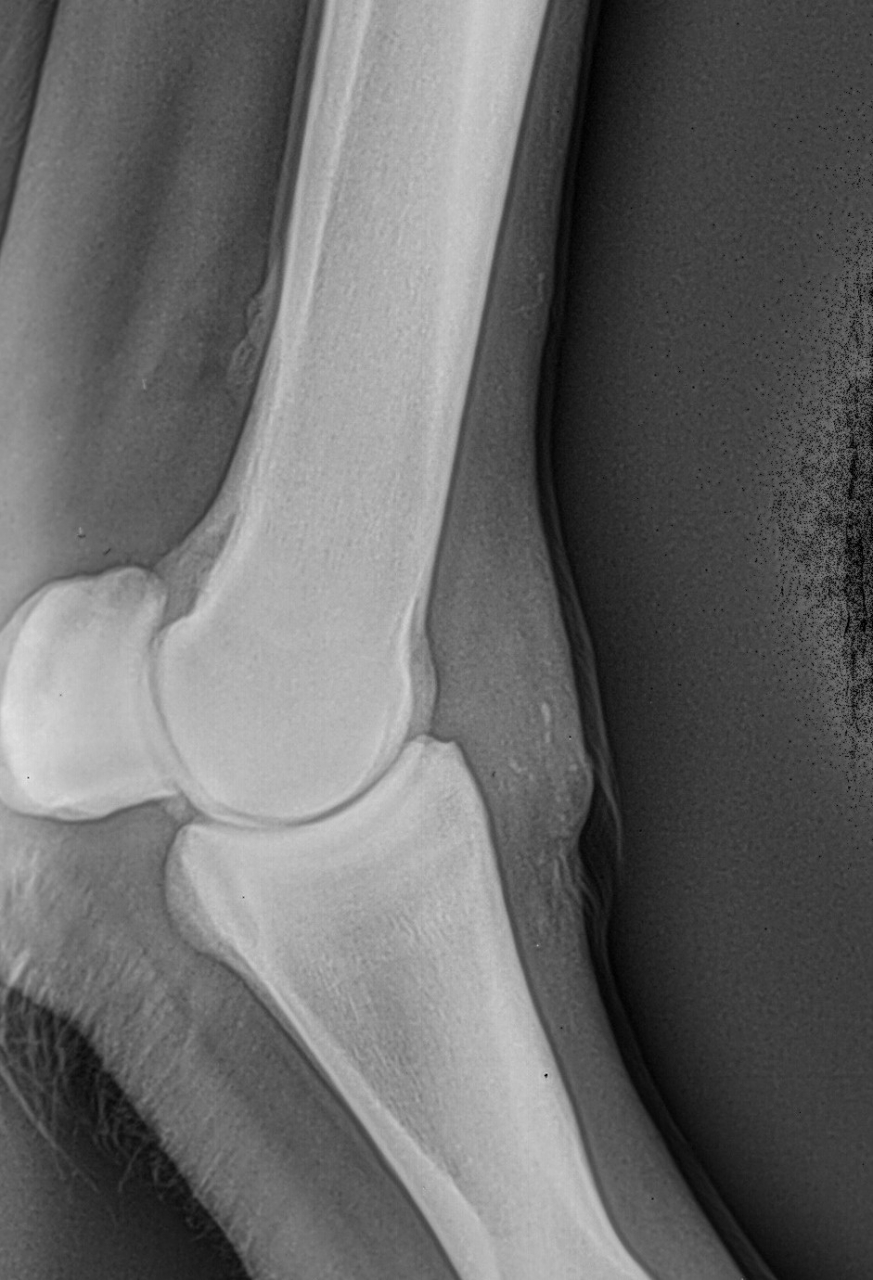

| Dire merci | Dimanche j'ai longé Cody et il est irrégulier au trot. Il a tendance à se coucher sur le cercle à main droite. J'ai du mal à voir d'où provient la boiterie. J'ai plus l'impression qu'il est raide. Je prends toujours le temps de l'échauffer au pas aux 2 mains et de faire un assez grand cercle. Je ne longe pas très longtemps. Avant que je l'achète il a eu une grosse plaie non soignée à l'antérieur droit. ![]() Lors de la visite d'achat du 12/12/2017, la véto a indiqué : Déformation des tissus mous en regard de l'épaississement cutané consécutif au chéloïde cicatrisé face dorsale du boulet, sans atteinte osseuse associée. J'ai fait réaliser des radios. ![]() ![]() La boiterie pourrait elle être une conséquence du chéloïde ? Les tendons sont normaux. Je vais sans doute faire passer l'osteo dans un premier temps. D'autres tests à faire pour déterminer l'origine de cette boiterie ? |

| Dire merci | Voici le compte-rendu du véto : Examen général: L’examen locomoteur au pas et au trot en ligne droite ne met pas en évidence de boiterie. Le cheval pose l’antérieur droit en deux temps : pose d’abord en muraille externe puis en interne. Une boiterie 2/5 de l’antérieur gauche apparait sur le cercle au trot à droite Examens complémentaires : Radiographie : Pieds de face : 3-4 fossettes synoviales sur le bord distal du naviculaire antérieur droit, de profondeur faibles et peu ouvertes. 2-3 fossettes synoviales dont l’une plus ouverte sur le bord distal du naviculaire antérieur gauche Léger pincement articulaire p1-p2 et p2-p3 coté externe visible sur le membre à l’appui. Boulet de face : Petit remaniement osseux au niveau de l’insertion proximale du ligt coll int Boulet et pieds ant droit de profil : ras La boiterie étant trop légère pour préciser la localisation par anesthésie étagée, plusieurs hypothèses sont envisagées. Par ordre d’importance : • Pincement et fatigue articulaire lié au parage ou à une compensation d’une légère entorse boulet • Entorse du boulet • Début syndrome podotrochléaire Message édité le 14/05/19 à 18:37 |